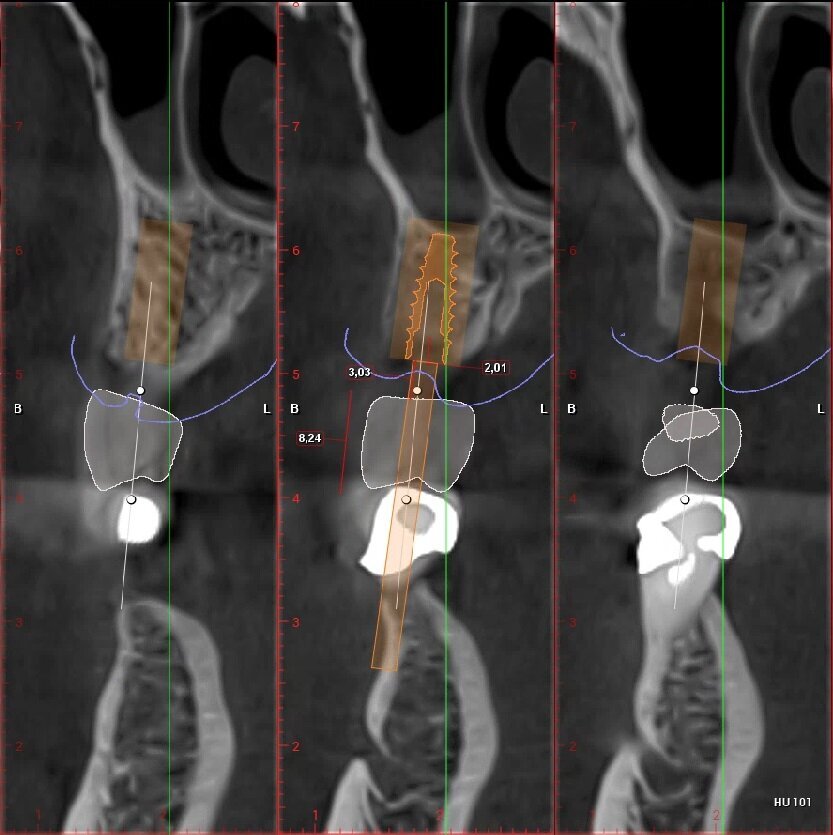

Fig. 4_Ceratura diagnostica elemento 2.5. Dimensione corono-apicale della corona congruente con elemento controlaterale 8,24 mm, tragitto trans-mucoso 3,03 mm, entità della rigenerazione ossea verticale necessaria 2,01 mm.

Fig. 5_Ceratura diagnostica elemento 2.6. Dimensione Corono-apicale della corona congruente con elemento controlaterale 8,00 mm, tragitto trans-mucoso 3,01 mm, entità della rigenerazione ossea verticale necessaria 2,81 mm.

_Pianificazione implantare

Posizionamento protesicamente guidato dell’impianto, tenendo conto dello spessore dei tessuti molli; che idealmente dovrebbe essere intorno ai 2-3 mm. Con valori più alti di 3-4 mm è indicata una ricostruzione ossea verticale al fine di riportarne la lunghezza in un range di normalità (Figg. 6, 7).

Fig. 6_Pianificazione implantare protesicamente guidata dell’elemento 2.5.

Fig. 7_Pianificazione implantare protesicamente guidata dell’elemento 2.6.